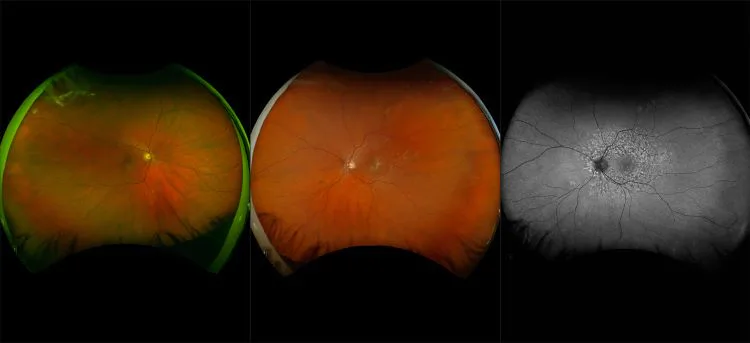

MonacoPro - Dry AMD, RG, OCT

Age-related macular degeneration is found in two forms 1. Dry early form. 2. Wet (serous leakage or whole blood). Early dry form typically has drusen (usually around 63u) and RPE degeneration and only needs periodic follow-ups, intermediate dry form has large drusen (>125u) and RPE degeneration and proliferation which requires examinations every 3 to 6 months depending on the severity of the presentation.